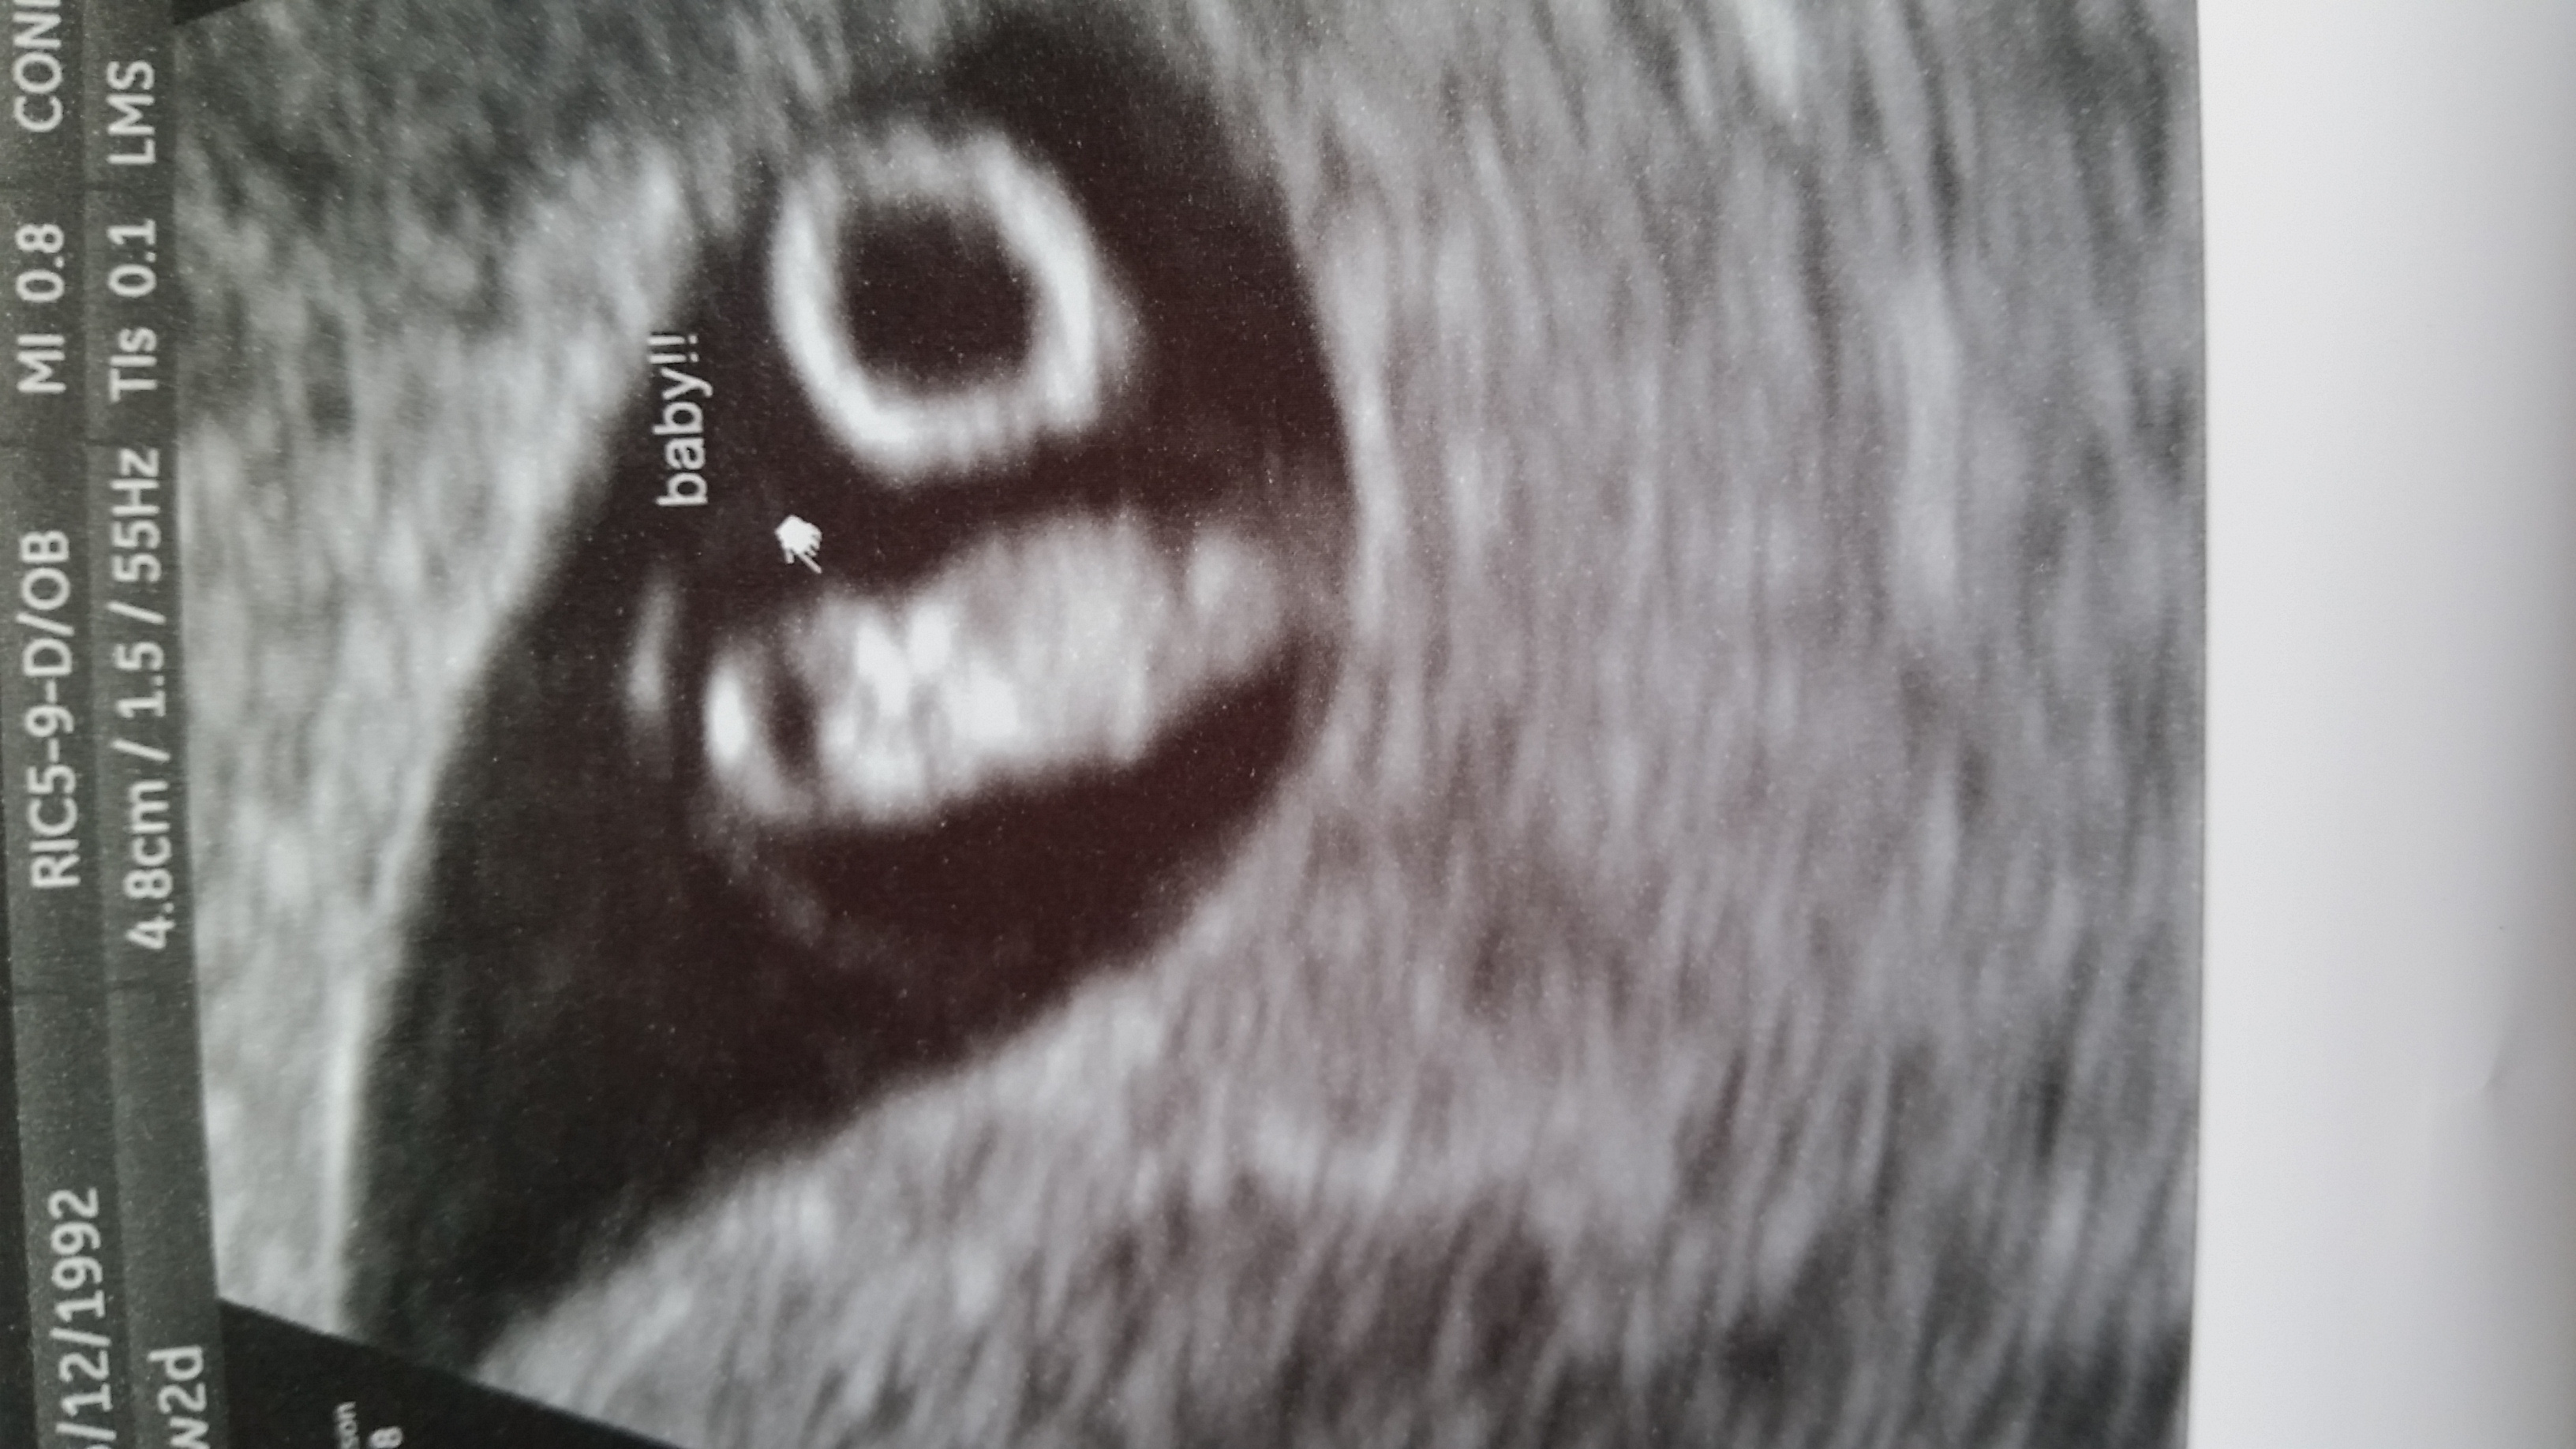

Had our first ultrasound today. Baby measured one day ahead, so exactly 9 weeks. My new edd is March 31st. Heart beat was 189 BPM. We got to see and hear its little heart beating!